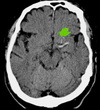

18

Q

q evalúa perfuTC para evc isquemico

A

core y penumbra

19

q evalúa angioTC para evc isquemico

vaso trombosado y colaterales

Que signo es el q se ve y de q tipo nos habla

ACM EVC isquemico en fase hiperaguda